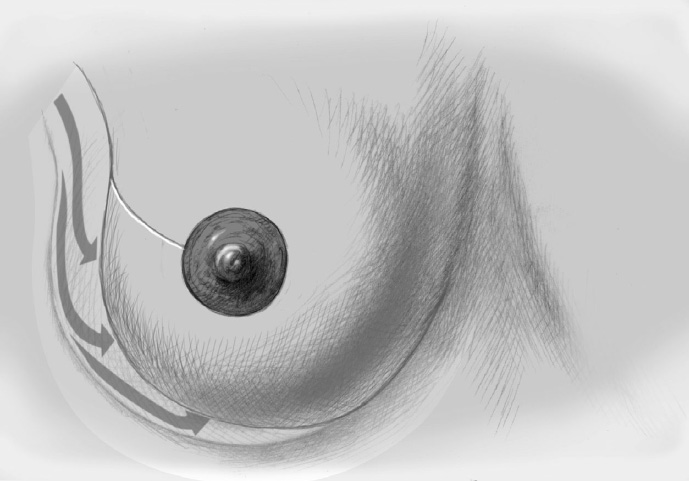

The skin is incised over the tumor region as far as possible (depending on surgeon, tumor size, tumor location, and subsequent treatment). A radial incision may be useful for tumors located in the lower quadrants or directly in the axillary tail of the breast. If the tumor is just beneath the skin, an island of skin over the tumor should be resected also. This can be achieved with both an elliptical semicircular incision and a radial incision. Another form is a purely periareolar incision when the tumor is in a relatively central position (see illustrations below).

The adjacent parenchyma is mobilized subcutaneously so that the defect can be filled with lobes of breast tissue. Mobilization means exposing the breast relative to the skin or muscle to achieve adequate mobility of < 25% or > 25% as required.

To cover the defect, the glandular lobes are mobilized from the adjacent parenchyma after subcutaneous dissection. The principle of intramammary lobe creation is to mobilize large parts of the breast (> 25%) either relative to the skin or relative to the pectoralis muscle. This “liberation” of the breast from one of its two planes of fixation allows adequate dissection and rotation of sufficient breast tissue. The Y-flap and rotation flap shown in Chapter 3.2.1 are examples of intramammary dissection.